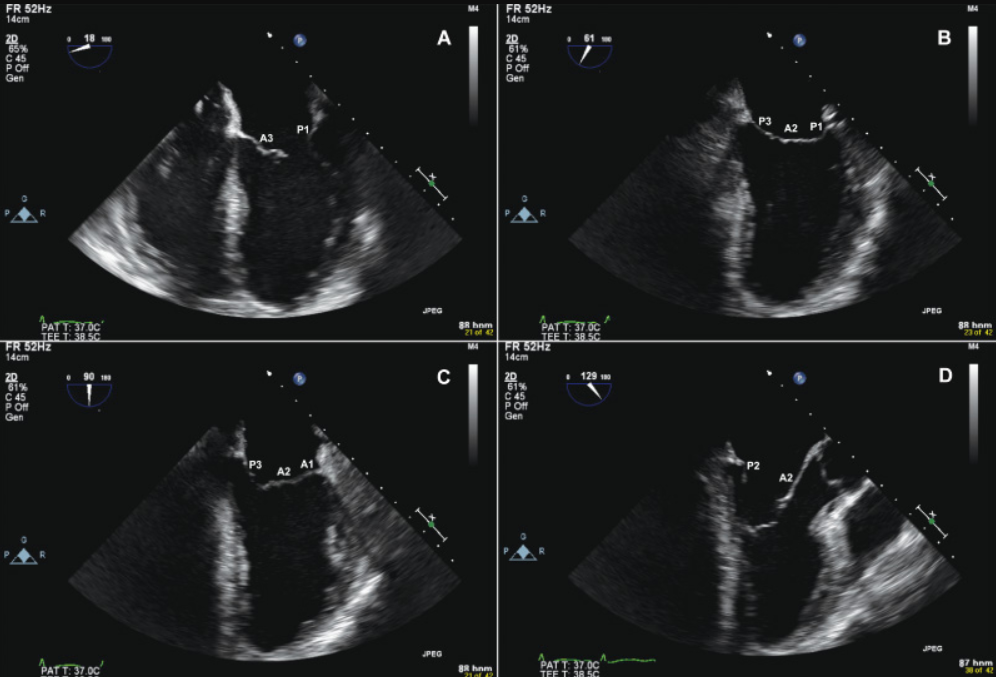

- Siêu âm tim qua thực quản: Phương pháp này ít được sử dụng, bác sĩ sẽ dùng đầu dò mỏng hơn gắn vào đầu của ống nội soi. Ống này sẽ được đưa vào thực quản giúp bác sĩ khảo sát tốt hơn các chi tiết của tim từ phía sau.